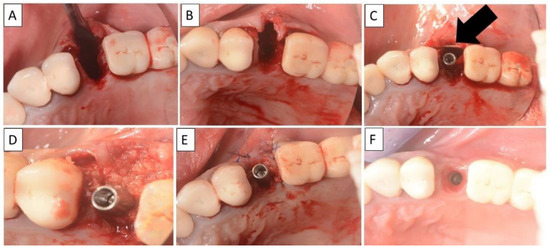

For each case, a minimally invasive buccal and palatal flap elevation was performed, followed by a thorough debridement of the extraction site. A periosteal releasing incision was performed on the buccal flap, 1 mm apical to the lower border of the defect. An immediate implant was placed with a high insertion torque. A sterile magnesium membrane (NOVAMag® membrane, botiss biomaterials GmbH, Berlin, Germany) with an initial thickness of 140 µm and dimensions 30 × 40 mm was prepared. The membrane was trimmed to size using the NOVAMag® scissors (Carl Martin GmbH, Solingen, Germany) (Figure 1A), ensuring smooth rounded edges to avoid sharp points that could perforate the soft tissue. The rim of the membrane is flattened using the NOVAMag® sculptor (Carl Martin GmbH, Solingen, Germany) (Figure 1B). The membrane was then either placed as a singular layer, or bent in half into a double layer of the membrane to improve its mechanical stability. The shape of the membrane was then bent according to contours of the defect using the NOVAMag® sculptor (Figure 1C). The membrane was then inserted into the socket as an extension of the buccal plate. The defect was filled with allogenic granular bone substitute (maxgraft®, botiss biomaterials GmbH, Berlin, Germany) and a collagen membrane (Jason® membrane, botiss biomaterials GmbH, Berlin, Germany) placed over the top of the augmentation and the flaps were sutured (Figure 1D,E). Closed wound healing is recommended with the magnesium membrane, as exposure can cause an accelerated resorption time. Suturing was performed with Nylon 5-0 sutures, using single interrupted and vertical mattress suturing techniques. Then, implants were immediately loaded (Figure 1F).

Figure 1.

For the magnesium shield technique, the magnesium membrane is first cut to shape using the NOVAMag® scissors (A). The rim of the membrane is then flattened using the NOVAMag® sculpture (B) and bent into shape (C). In a compromised extraction socket (D), the membrane is either place as a single layer or bent into a double layer, before being positioned to rebuild either the buccal or palatal wall. The membrane is held in position by the periosteum and the defect space is filled with the graft material. A collagen membrane is placed on the top of the ridge (E). Using the technique, it is also possible to immediately place implants with a provisional restoration (F). Once implanted, the magnesium membrane will begin to degrade, transforming into magnesium salts that maintain the soft tissue barrier, and hydrogen gas will be released that provides a tenting of the soft tissue, which also extends the barrier effect, since cells cannot cross the gas cavity (G). After the magnesium metal has transformed into magnesium salts, no more gas is released, and the soft tissue returns into position over the newly formed bone and magnesium salts (H). After the critical healing period, the magnesium membrane is completely resorbed (I).

Nontraumatic extraction of tooth 21 (Figure 6), followed by bone augmentation using the magnesium membrane shield technique to rebuild the buccal wall as described in Section 2. The implant was immediately covered with a provisional crown due to its location in the aesthetic zone.

Figure 6.

(A,B) Alveolar socket following atraumatic extraction. Severe bone loss of buccal plate. (C) Buccal plate was created using the magnesium membrane double layer technique. (D) Application of allograft. (E) closing sutures and immediate provision. (F) four months postoperatively there was an excellent regeneration of bone defect, including fully regenerated cortical and palatal plates. The implant was stable and there was a good healing of the soft tissues. Black arrows are used to indicate the position of the magnesium membrane.